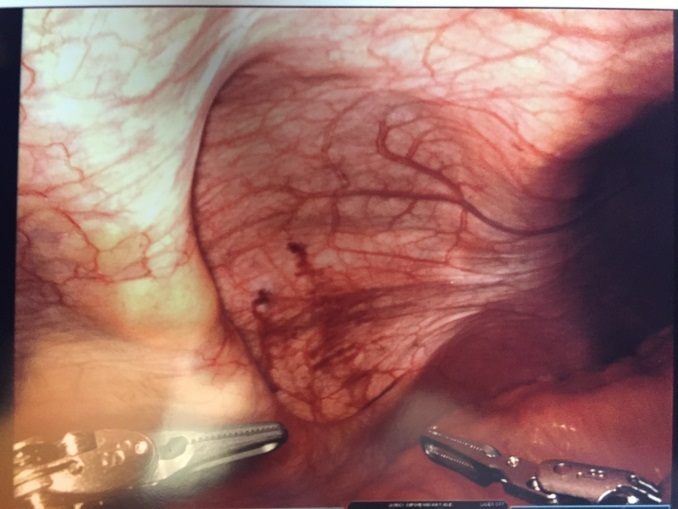

Patient #1: The patient was placed in supine position, airplaned to the left at 30 degrees, and placed in a reverse Trendelenburg position (body is flat while the head is elevated 15-30 degrees higher than the feet). A peri-umbilical Veress (situated or occurring adjacent to the navel) entry was made into the peritoneal cavity and the abdomen insufflated to 15 mmHg. A peri-umbilical 8 mm. robotic trochar was placed and the abdomen inspected for any iatrogenic injuries and none were noted. Two additional 8 mm working ports were also placed, one in the right lower quadrant, and one in the epigastrium. A da Vinci surgical system Xi (Intuitive Surgical, Inc. Sunnyvale, CA) robot was then docked and the area inspected. The hernia contents were easily reduced and revealed no evidence of ischemia or perforation (Figure 3).